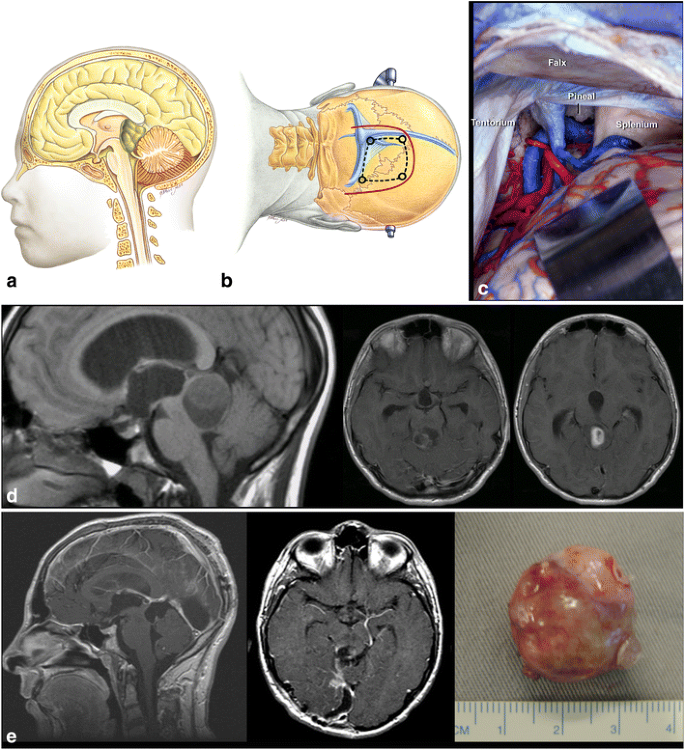

Fig. 6

figure 6

a. Tumors located at the central portion of the midbrain and growing towards the pineal region. b Infratentorial supracerebellar approach. c Anatomical view of pineal region via the infratentorial supracerebellar route. SC superior colliculus, IC inferior colliculus

Fig. 10

figure 10

a Tumor in the quadrigeminal plate growing towards the fourth ventricle. b Transtentorial occipital approach. c Right occipital transtentorial view. The pineal gland and splenium are exposed. d. Quadrigeminal plate tumor growing towards the fourth ventricle, operated via transtentorial-occipital approach. e. Postoperative imaging 9 years after gross total resection of the lesion, showing no evidence of tumor, which was a pilocytic astrocytoma